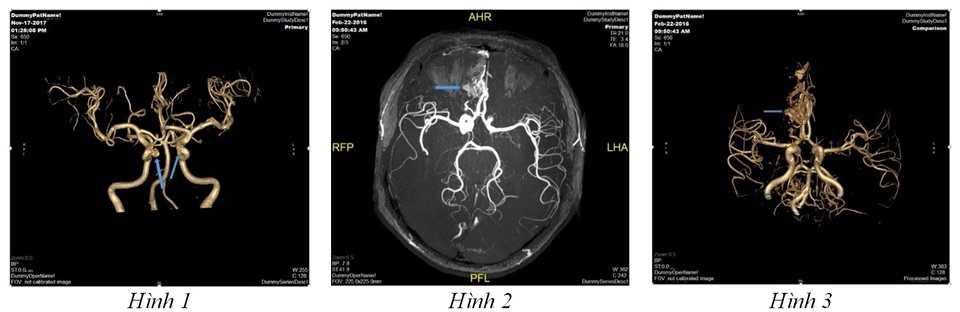

Hình 1: Hình ảnh chuỗi xung mạch não (MRA tof 3D) của một bệnh nhân nữ 54 tuổi sàng lọc mạch não phát hiện túi phình động mạch (vị trí mũi tên) và đã được can thiệp nút túi phình động mạch não phải tại Vinmec. Hình 2 và hình 3: Hình ảnh dị dạng thông động tĩnh mạch vùng trán phải của một bệnh nhân nam 40 tuổi. Bệnh nhân đã được can thiệp nút khối dị dạng tại Vinmec và hồi phục sức khỏe tốt.